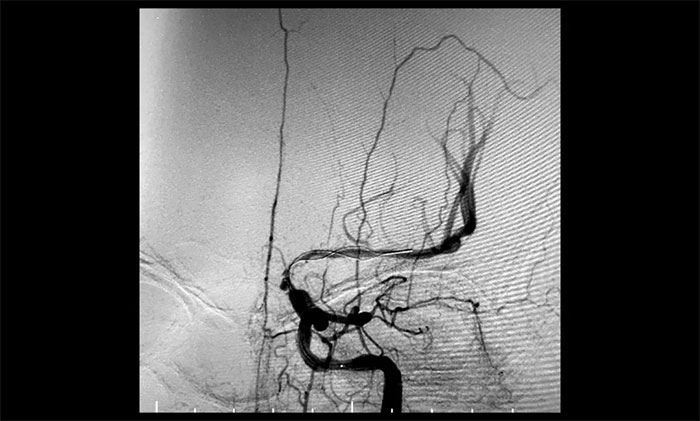

術后一個月,經(jīng)過綜合治療,患者病情穩(wěn)定。10月11日,再次行經(jīng)皮左側頸動脈慢性閉塞開通術,腦保護傘下左側頸動脈支架置入手術,經(jīng)皮左側頸動脈球囊擴張成形術。術中造影顯示,左頸內(nèi)動脈起始段多發(fā)重度狹窄,左頸內(nèi)動脈前向血流慢,左頸內(nèi)動脈巖骨段中度狹窄,左頸內(nèi)動脈眼動脈段、后交通段多發(fā)重度狹窄伴次全閉塞。

對于長節(jié)段頸動脈慢性閉塞再通,血栓逃逸是一個很重要的問題。由于患者左側頸內(nèi)動脈多處串聯(lián)病變,閉塞段血栓負荷量大,保護傘無合適著陸位置,手術風險極大,難度極高。

術中,席剛明教授、王貴平博士采用COSIS技術,在保護傘無法到位的情況下,利用Syphonet®取栓支架作為顱內(nèi)的遠端保護裝置,減少栓子逃逸,同時利用Syphonet®取栓支架的輸送導絲完成微導管交換、球囊擴張、支架置入等操作,減少器械交換,降低并發(fā)癥的發(fā)生。

經(jīng)微導絲成功進入狹窄、閉塞頸內(nèi)動脈,在支架保護下,進行球囊逐段擴張,支架置入……,經(jīng)多次球囊擴張,置入支架后,造影顯示左頸內(nèi)動脈起始段狹窄明顯改善,左頸內(nèi)動脈顱內(nèi)段順利再通,左頸內(nèi)動脈眼動脈段、后交通段狹窄明顯改善。造影及3D造影見左頸總動脈、左頸內(nèi)動脈、左大腦中動脈顯影可,行支架CT見顱內(nèi)支架成形可,手術取得成功!

▲ 術后,右頸內(nèi)動脈起始段狹窄明顯改善